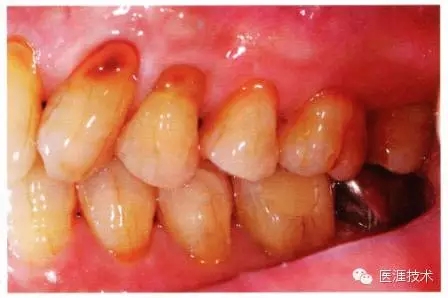

圖為50歲女性,無特殊全身疾病,不抽煙。持續(xù)保養(yǎng)6年。無填充物等問題,依照患者本人要求持續(xù)觀察。牙周組織臉頰側(cè)雖見部分萎縮,但X線牙片顯示牙間無骨吸收現(xiàn)象,保持著比較健康的狀態(tài)。